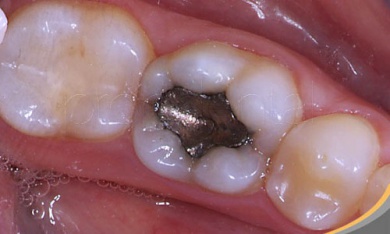

L’ amalgama dentale è un materiale di colore argentato che combina vari metalli, principalmente il mercurio.

Viene utilizzato dagli odontologi per riempire le cavità che si formano in seguito alle carie.